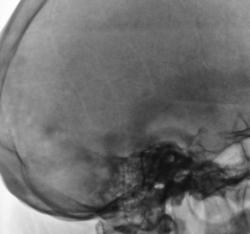

Представлены, на диске, такие изображения черепа. Что посоветуете уважаемые коллеги?

Уважаемый  Валентин Львович, я так понимаю Вас смущает ячейки лобной пазухи? В данном случае надо обратить внимание на толщину костей крыши черепа, а следовательно и на турецкое седло, следует проконсультироваться у эндокринолога с дальнейшим проведением МР-исследования гипофиза.

Структура затылочной кости не совсем обычная...похоже на "пробойниковые отверствия"...касаемо лобных пазух - такой "фасон", мне кажется это природа, и мало вероятно, что ендокринология...

Кости свода толстоваты, пазухи крупные. Турецкое седло не изменено. По-моему, стоит беспокоиться, только если есть эндокринные нарушения.

Файзуллин, если мне не изменяет память, частенько, гиперпневматизацию пазух связывал с опухолевым ростом. Но в данном случае, по всей видимости, вариант или аномалия развития лобной пазухи.